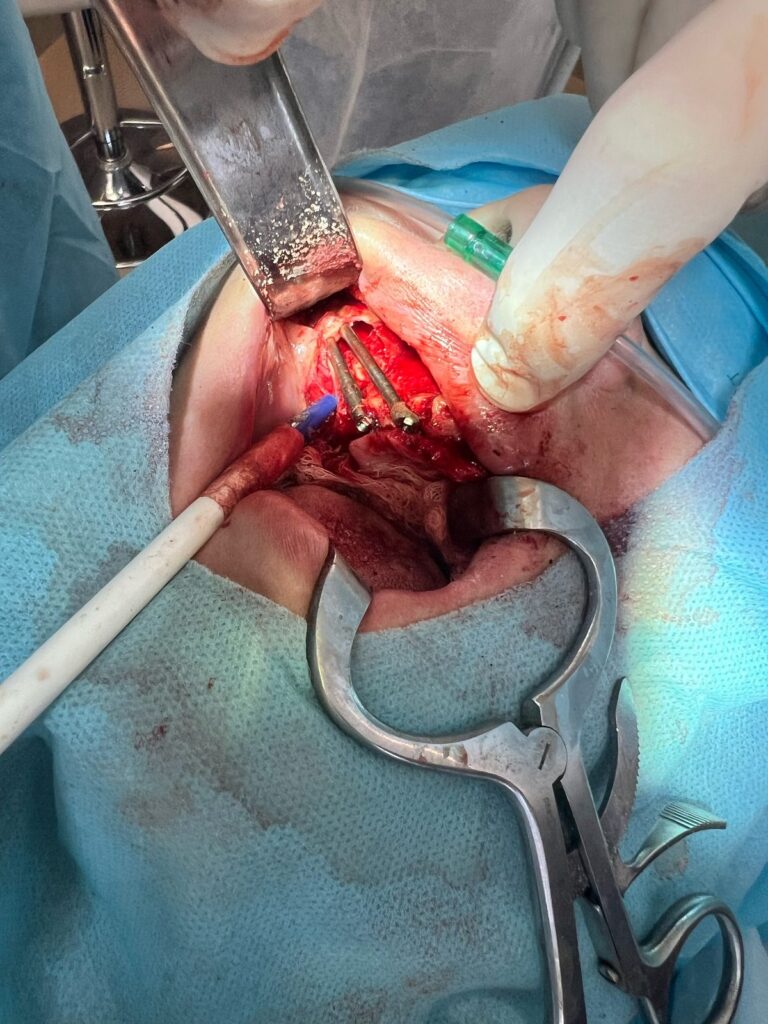

CORSO DI IMPLANTOLOGIA E CHIRURGIA ORALE RICOSTRUTTIVA AVANZATO

100% Chiruriga su pazienti

2. Tecniche All-on-4 e All-on-6

3. Grande rialzo del Seno Mascellare

4. Trasposizione dei mentonieri

5. Prelievi ossei e Tecniche Ricostruttive

CORSO DI IMPLANTOLOGIA ZIGOMATICA

3 CASI ZYGOMA GARANTITI

1. Impianti Zigomatici

2. Implantologia Nasale e Pterigoidea